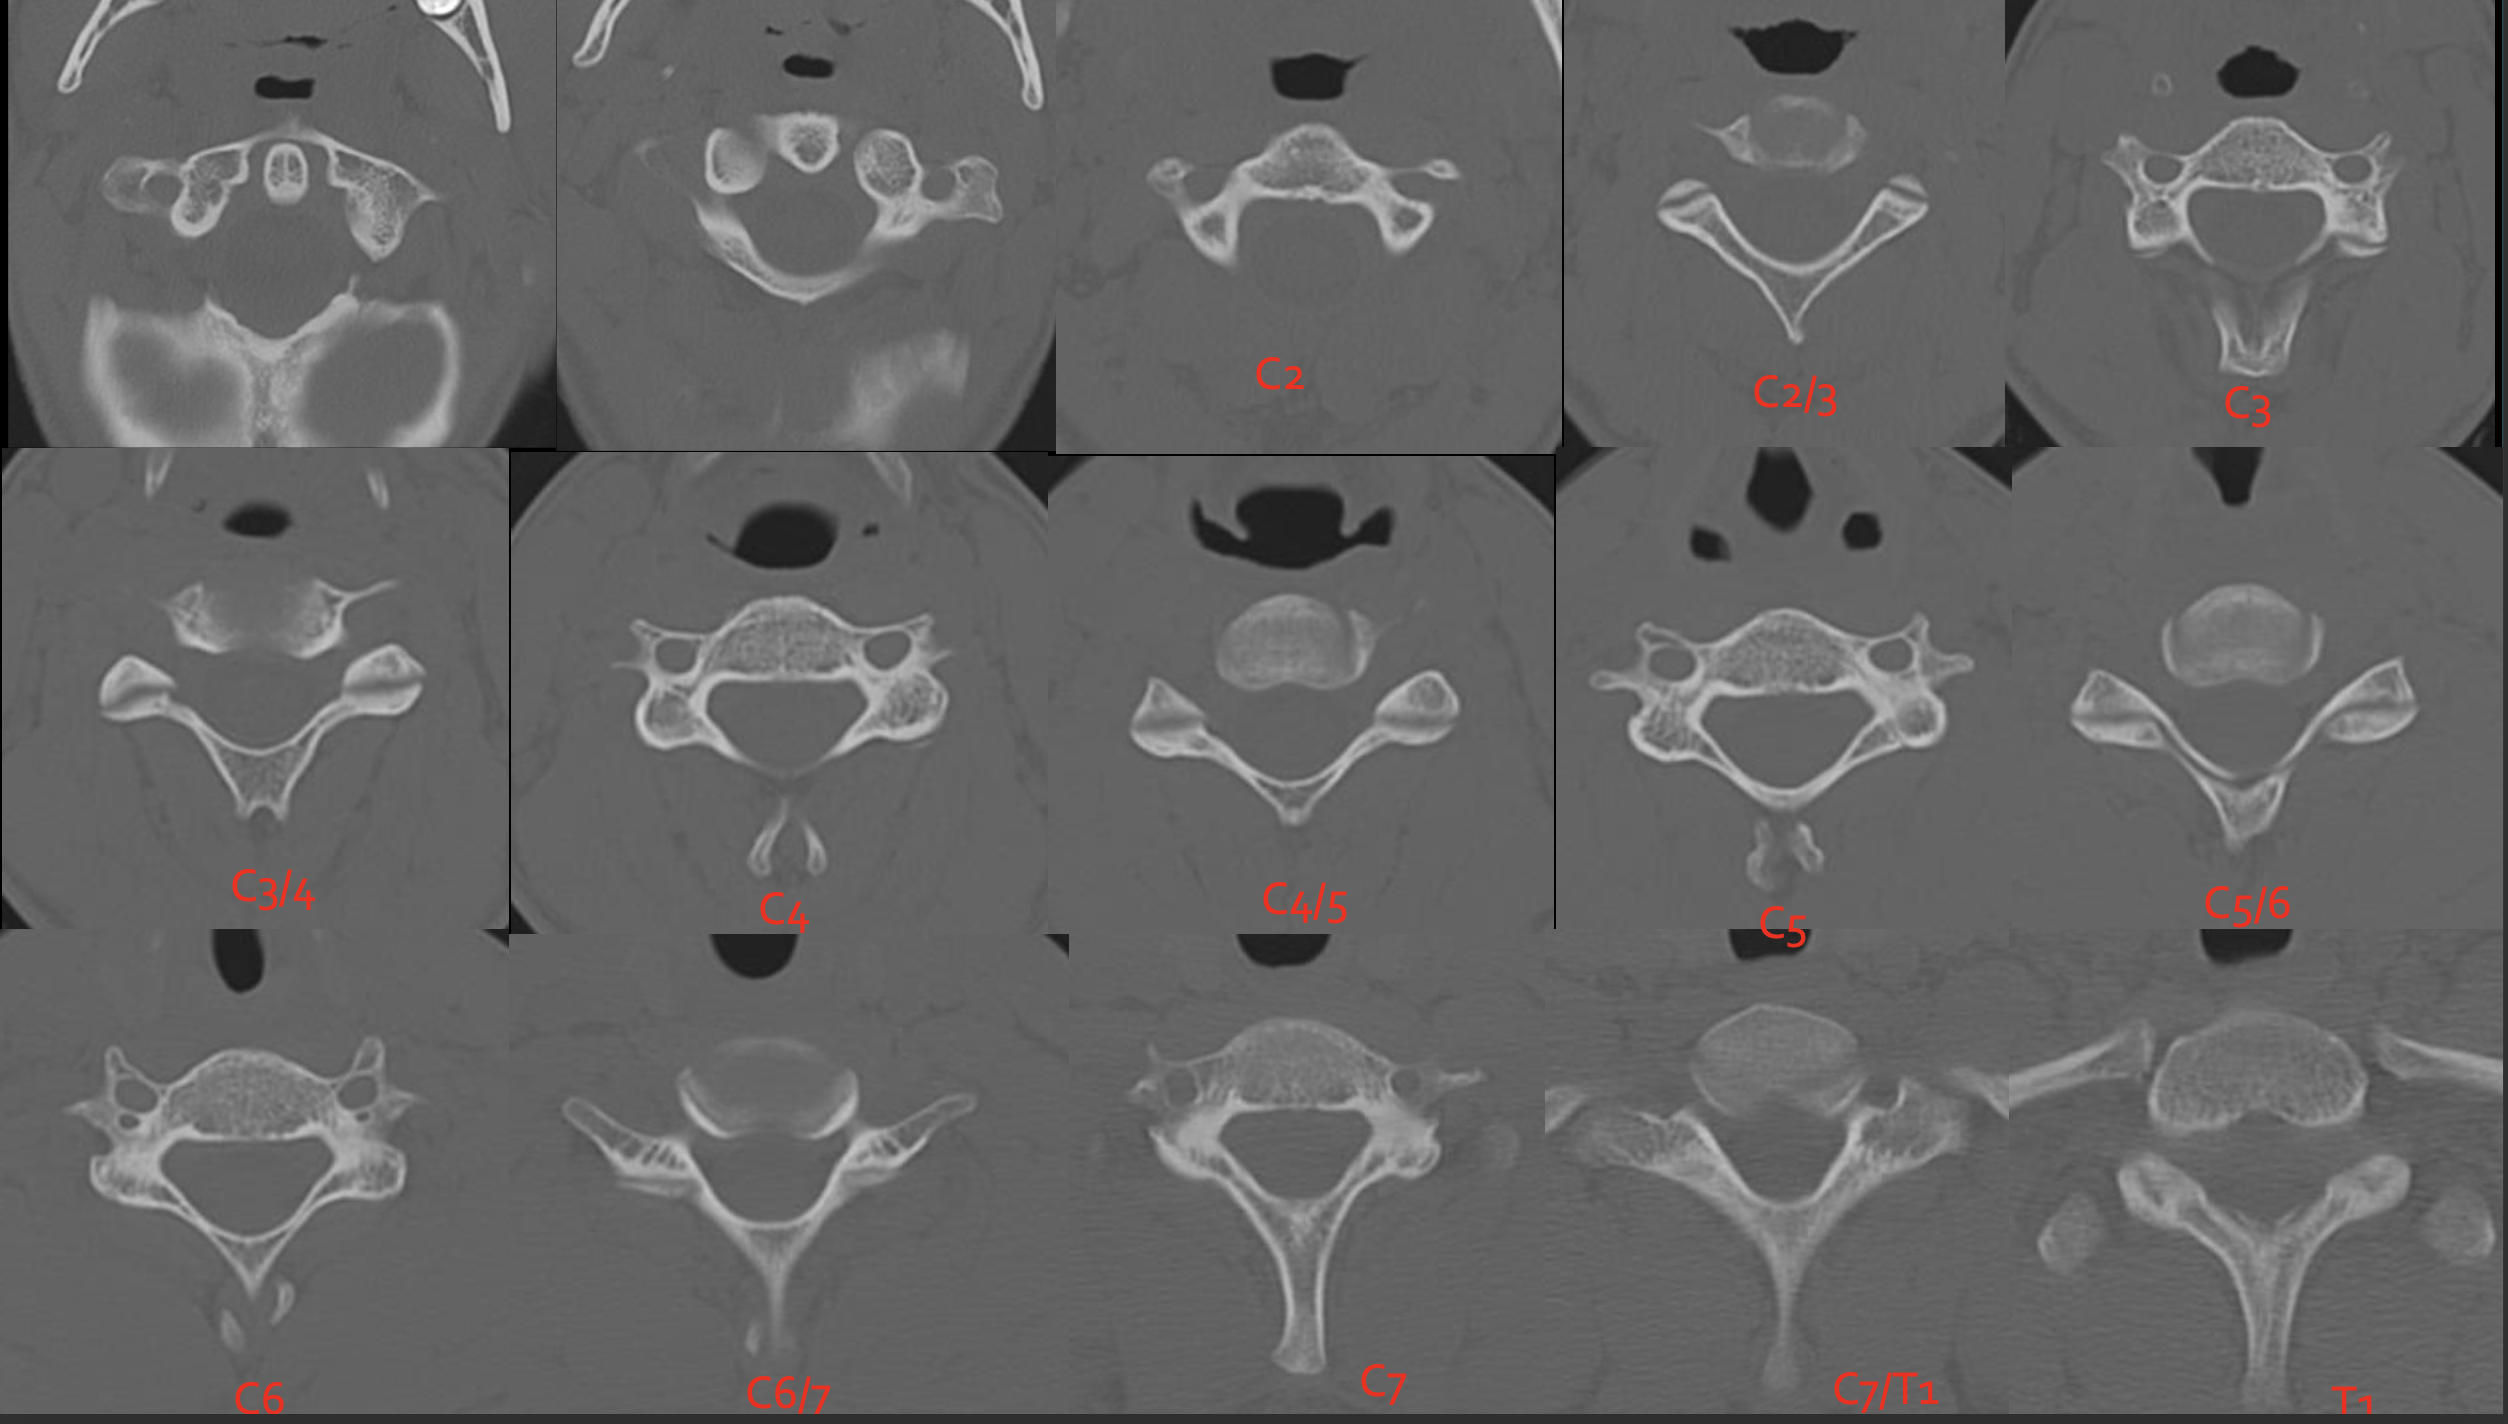

C2

C3

C4

c5

c6

c7

T1

C1